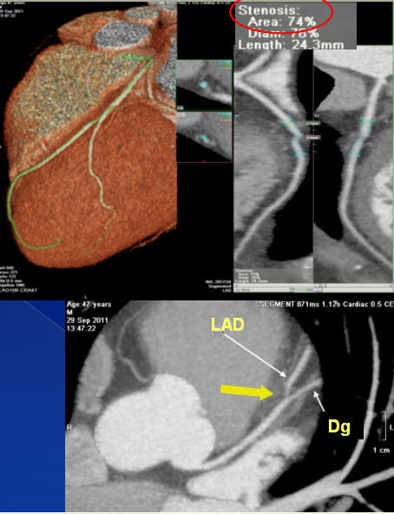

The results showed that 55% of the patients had atherosclerosis, 49% had no significant lesion, and more than 6% had significant lesions (> 70% luminal narrowing), he said. Age, male gender, diabetes, serum cholesterol, smoking, and hypertension were related to the presence of atherosclerosis.

As for major adverse events, there was one sudden death, one myocardial infarction requiring stent implantation, one percutaneous coronary intervention, two cases of unstable angina, and three cases of atypical chest pain -- and all these patients had nonobstructive atherosclerotic plaque at CTA. The results are in line with other data such as the Coronary CT Angiography Evaluation for Clinical Outcomes (CONFIRM) registry, in which patients with a nonobstructive lesion at CTA had higher mortality than patients with no plaque, Hidalgo said.

The patient who died, for example, was a smoker with moderate hypertension who had "a couple of plaques in the proximal [left anterior descending artery], but no significant lesions," he said. The cause of death was unknown, and perhaps not of cardiovascular origin, he added.